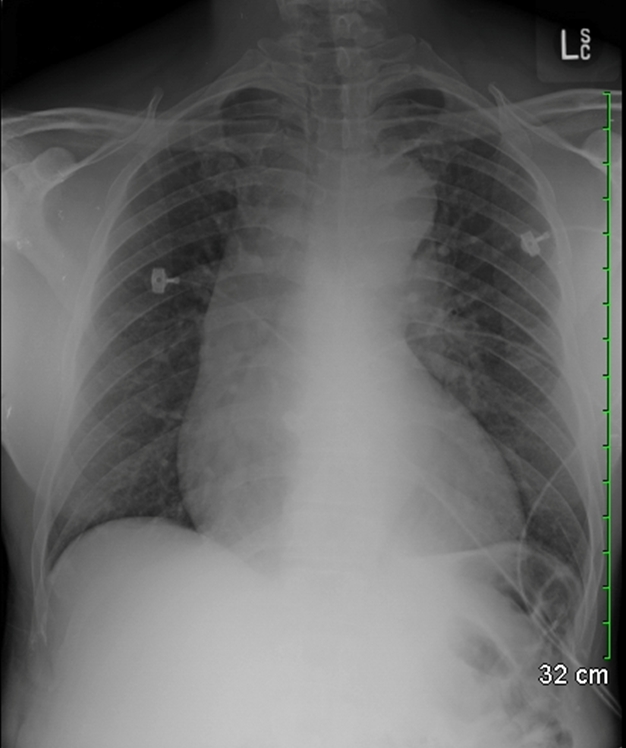

A 72-year-old man is seen in the emergency department due to chest pain. He reports 2 days of mid-sternal chest pain, left shoulder pain, fatigue, and occasional sweating. He sleeps on his right side because sleeping on his back "hurts too much." He has a known history of coronary artery disease and underwent coronary artery bypass grafting (CABG) 4 weeks ago. The post-operative course was complicated by new-onset temporary atrial fibrillation and several days of post-operative fever.

His temperature is 38.2 C (100.8 F), blood pressure is 120/75 mmHg, pulse is 89/min, and pulse oximetry is 96% on room air. His cardiac and pulmonary examinations are within normal limits. His chest examination reveals a well-healing sternotomy site with mild erythema, but no tenderness to palpation.

ECG shows sinus rhythm with left bundle branch block, which was present on his ECG three weeks ago. Chest x-ray reveals cardiomegaly with sternotomy wires present and a small left-sided pleural effusion.

Which of the following best explains this patient's current complaints?

This patient's clinical presentation is consistent with postpericardiotomy syndrome (PCIS) after recent CABG. PCIS is likely due to surgical damage of the mesothelial pericardial cells with resultant blood in the pericardial space, which causes an autoimmune response against the released cardiac antigens. The immune complexes deposit and cause inflammation in the pericardium, pleura, and lung.

PCIS presents similar to acute pericarditis with typical pleuritic chest pain, pericardial friction rub, ECG changes, and/or new or worsening pericardial effusion. Most patients after cardiac surgery have some baseline ECG changes (such as LBBB in this patient), making it difficult to interpret the ECG for evidence of pericarditis. Patients who develop PCIS usually respond to NSAIDs; steroids maybe used for refractory cases. Giving colchicine after cardiac surgery significantly decreases the incidence of PCIS.

(Choice D) Hospital acquired pneumonia would be less likely in this patient 4 weeks after hospitalization with a normal pulse oximetry and pulmonary examination. A small left-sided pleural effusion is commonly seen after cardiac surgery, but there are no infiltrates on the chest x-ray to suggest pneumonia.